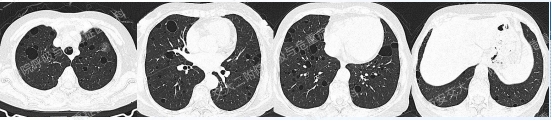

上图所示肺部多发囊性病变,双肺广泛分布,直径在2-10mm之间,壁薄,囊壁间组织相对正常。结合育龄期女性等临床资料,不难诊断淋巴管平滑肌瘤病(LAM)。对疑似LAM的女性的初步评估还应包括血管平滑肌脂肪瘤的筛查、淋巴管受累以及是否存在未被诊断的结节性硬化症。该例患者经评估后诊断散发型S-LAM。